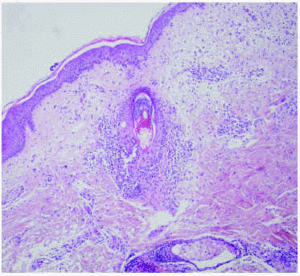

Se realizó una biopsia de una de las lesiones del tórax, donde se observaba un denso infiltrado neutrofílico, con células linfohistocitarias alrededor y en el seno de los folículos pilosos, con formación de pústulas en las zonas más superficiales de éstos (fig. 4). El diagnóstico histológico fue foliculitis aguda pustulosa. Asimismo, se tomó una muestra para cultivo bacteriano de una de las lesiones pustulosas, en la que creció Staphylococcus epidermidis.

Fig. 4.--Histología: infiltrado neutrofílico y linfohistiocitario alrededor del folículo piloso, con formación de pústula superficial. (Hematoxilina-eosina, x20.)